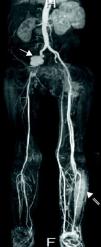

Case reportA 50-year-old man with a history of smoking, drug addiction and chronic hepatitis C went to the emergency department with asthenia, fever and headache of one month's evolution and abdominal pain for two days. On physical examination he presented fever; cardiac auscultation revealed a loud decrescendo diastolic murmur, grade III/VI, at the left sternal border; there were no signs of heart failure. Laboratory tests revealed acute renal failure (creatinine 2.5mg/dl and urea 60mg/dl compared to normal values one week previously), elevated C-reactive protein (77.5mg/l) and normocytic normochromic anemia (Hb 11.2g/dl). Abdominal computed tomography (CT) showed splenomegaly without visible infarcted areas and right hydrouretonephrosis caused by an aneurysm of the right common iliac artery (42mm maximum diameter). Transthoracic echocardiography (TTE) revealed a 15-mm vegetation on the non-coronary leaflet of the aortic valve (Figure 1) and severe aortic regurgitation (Figure 2), together with moderate to severe left ventricular systolic dysfunction (ejection fraction 35%); these findings were confirmed by transesophageal echocardiography. The patient was admitted to the cardiology department, where empirical antibiotic therapy was begun with vancomycin and meropenem; it was decided not to add an aminoglycoside due to his low glomerular filtration rate, estimated at 20ml/min/1.73m2. On the second day of hospital stay he showed signs of cognitive slowing, with no focal neurological alterations; subsequent cerebral magnetic resonance imaging (MRI) showed multiple recent cerebral infarcts. Amphotericin B-susceptible Candida albicans was isolated from blood cultures; antifungal therapy was begun and the surgical center was contacted in order to transfer the patient for aortic valve replacement. While awaiting transfer, he suddenly suffered intense pain, coolness and loss of pulses in his left leg due to acute ischemia, probably caused by cardioembolism from the fungal vegetation. He was transferred urgently to a vascular surgery center where distal left patellofemoral embolectomy was successfully performed. The patient was then transferred to the cardiothoracic center and the aortic valve was replaced by a bioprosthetic valve. Microbiological analysis of the aortic valve and the embolus removed from the left femoral artery revealed C. albicans. Postoperative TTE showed normal aortic prosthetic valve function and after 14 days the patient was transferred to the cardiology department of our hospital. During hospitalization he presented fever and elevated inflammatory markers; repeat TTE confirmed normal prosthetic valve function, with no evidence of vegetations. MRI of the abdomen and lower limbs detected a large pseudoaneurysm of the right iliac artery, the external iliac artery being occluded distal to the pseudoaneurysm, multiple swellings compatible with abscesses in the left groin and thigh (the access site for the previous vascular surgery), and abscesses in the anterolateral muscle compartment of the left leg (Figure 3). In view of the existence of a focus of infection and the absence of evidence of endocarditis on TTE, it was decided not to perform transesophageal echocardiography. The patient was transferred to the vascular surgery department, where he underwent total aneurysmectomy with femoro-femoral crossover bypass using an inverted right greater saphenous vein graft, together with exploration and drainage of the abscesses in the left leg. Microbiological study of the pseudoaneurysm revealed Staphylococcus epidermidis. During hospitalization in the vascular surgery department intermittent fever persisted and the patient's general condition progressively deteriorated. S. epidermidis was detected in repeat blood cultures and broad-spectrum antibiotic therapy was begun with vancomycin and meropenem. CT of the pelvis and thighs revealed two new pseudoaneurysms, in the left internal iliac artery and the left superficial femoral artery. The patient underwent further surgery, during which it became clear that the clinical situation had progressed rapidly, with rupture of the left femoral pseudoaneurysm and extensive hemorrhagic infiltration and abscesses in the thigh. The left internal iliac and left superficial femoral arteries were ligated and devitalized tissue and purulent collections were thoroughly debrided. Late in the procedure it was decided to proceed to open transfemoral amputation of the leg, due to gangrene. The patient remained in the vascular surgery department for four months, during which antifungal therapy was maintained; transfemoral reamputation was performed and surgical debridement of abscesses in the stump were required on several occasions. After partial closure of the residual limb he was discharged, clinically stable; it was decided not to continue antifungal therapy due to its possible hepatic toxicity and the patient's chronic hepatitis C.

Four months after discharge, the patient was admitted to the emergency department with fever and abdominal pain. Abdominal CT revealed multiple renal and splenic infarcts and celiac trunk embolization (Figure 4). TTE showed an 8-mm vegetation on the aortic prosthesis and moderate aortic regurgitation. He was transferred to the cardiothoracic surgery department for emergency surgery, but suffered cardiac arrest before reaching the operating room. Blood cultures from the emergency department revealed the presence of C. albicans.